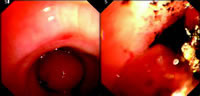

钬激光是以稀有金属钬为激发介质的固态脉冲式激光,已在耳鼻喉科、泌尿外科及妇科新生肿物的治疗上应用多年。但将其应用于中心气道内增生性病变的切除,在国内外尚鲜有报道。我们在1997年10月至2007年6月期间,经软质支气管镜对32例患有中心气道阻塞的患者进行新生肿物的钬激光切除,取得了良好的效果(图1,2)。

共有40处病变,有效切除病变的成功率分别为:气管内病变100%,主支气管94%;良性病变100%,恶性病变93%。有24例患者存在中心气道严重阻塞及呼吸衰竭,这些患者在全身麻醉或机械通气下,经钬激光治疗后即刻获得缓解,喘鸣消失。